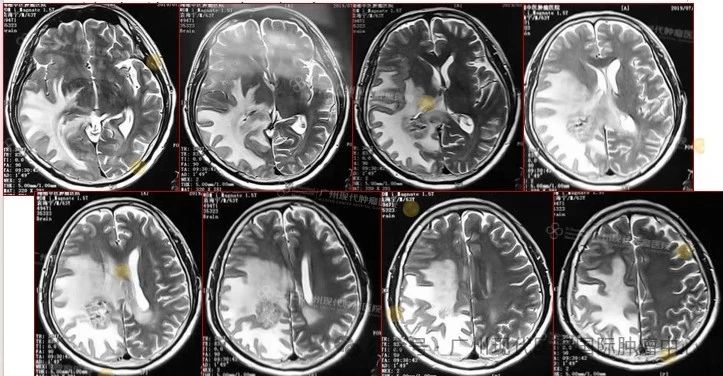

患者:63歲,男性

2013-11,體檢發(fā)現(xiàn)肺部腫瘤,

2015-11,頭顱MR檢查提示顱內(nèi)轉(zhuǎn)移

2018-11,顱內(nèi)腫瘤進(jìn)展,無(wú)法接受后續(xù)治療

2019-3,接受腦瘤粒子植入術(shù)

2019-7,顱內(nèi)腫瘤基本消失,正常生活至今

2019年7月,顱內(nèi)腫瘤已基本消失